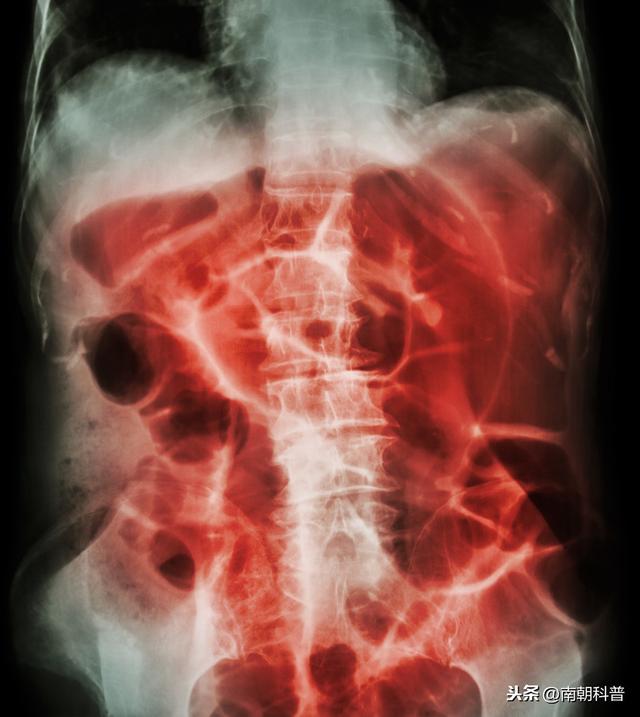

浠讳綍涓嶆槑鍘熷洜鐨勮吂鐥涳紝搴斿父瑙勮吂閮ㄥ钩鐗囨鏌ャ€傝吂鐥涘悗4-6灏忔椂鍑虹幇姘旀恫骞冲拰鏄庢樉鑲犵绉皵鎵╁紶鏃讹紝鍗冲彲璇婃柇鑲犳闃伙紝鍚屾椂锛岃繕鍙尯鍒槸灏忚偁姊楅樆杩樻槸澶ц偁姊楅樆銆佹満姊版闃昏繕鏄夯鐥规闃伙紝鍔ㄦ€佽瀵熷彲鍙嶆槧鑲犳闃荤殑鐥呮儏鍙樺寲锛屽洜姝わ紝鑲犳闃诲彂鐢熷悗鏈€濂芥瘡1-3澶╂媿涓€寮犺吂閮ㄥ钩鐗囷紝鐩村埌姘旀恫骞冲拰鑲犵Н姘旀秷澶便€?/p>